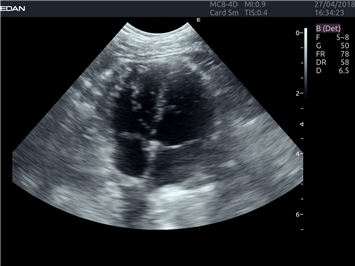

EDAN Acclarix LX4 VET представляет собой профессиональную ультразвуковую систему, специально разработанную для ветеринарных исследований. Сочетание стабильности, высокой производительности и эффективности делает эту систему идеальным выбором для современной ветеринарной практики.

• Мультилучевое сложно-составное сканирование (SCI):

• Повышенная четкость изображения

• Улучшенная визуализация сложных анатомических структур

Режимы акустической прозрачности 3D:

Да

Объемное сканирование:

B-режим, Двухмерное сканирование: